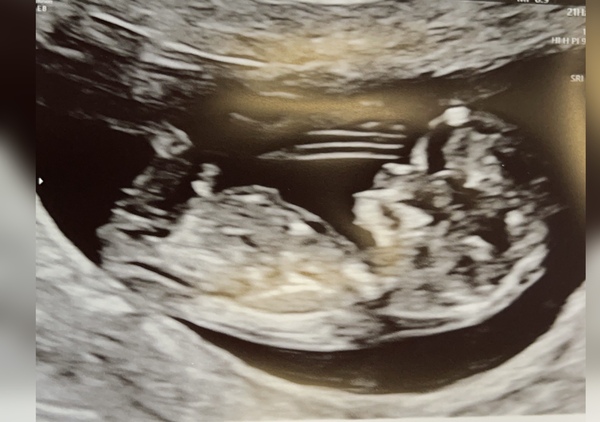

My 12 week scan that dated me at 11+1 which makes sense with my cycles. Got another scan next week as baby was teeny bit small but otherwise perfect. Due date 2nd August.